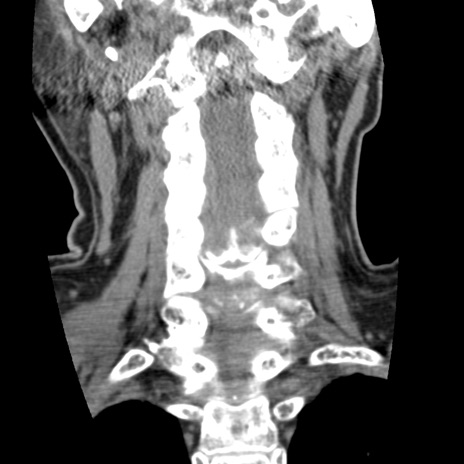

症例50 頚椎CT(冠状断像)

【症例】60歳代女性

【主訴】後頭部〜右後頸部にかけての痛み

【現病歴】本日飲食店でコーヒーを飲んでいたところ、突然後頭部〜右後頸部にかけて痛みが出現し、右上肢の感覚障害を伴ったため救急要請。

【身体所見】脳神経学的に明らかな異常所見を認めず。右上肢に軽度の感覚障害あり。

異常所見と診断は?

矢状断像